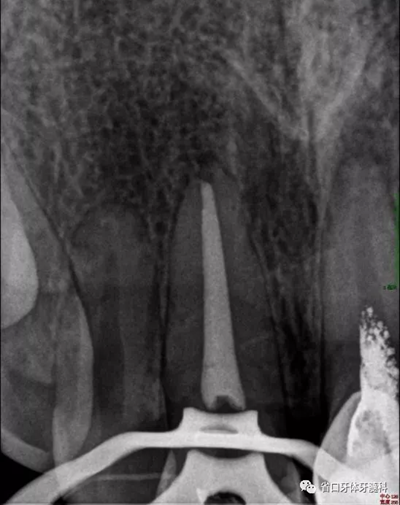

X線檢查:11冠部近中鄰面見(jiàn)高密度充填影像,邊緣有低密度線形暗影,根管內(nèi)見(jiàn)高密度稀疏影像,根管內(nèi)充填物與根管壁不密合,超出根尖孔約4-5mm,根尖周見(jiàn)低密度暗影;21根管上段修復(fù)體高密度影像,中下段根管空虛,根尖周見(jiàn)低密度暗影。圖3

圖3 治療前X線片